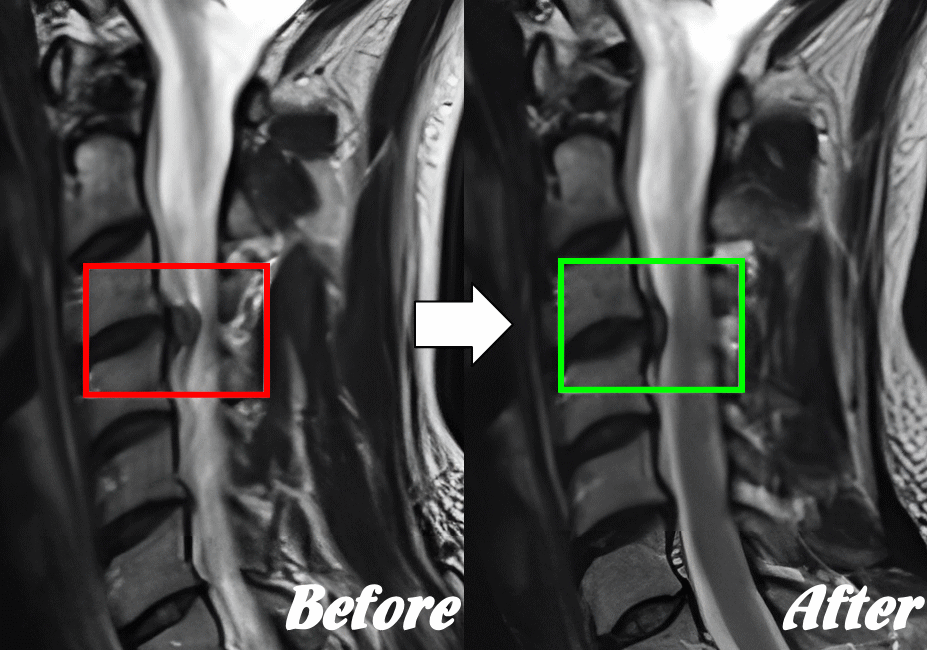

矯正により骨の配列を整えることで筋肉を弛緩させ、神経圧迫や血流障害を取り除く施術。体の痛みや痺れに有効です。

カイロプラクティックで行っていることは、深い層の筋肉と腱の高速ストレッチです。

骨/関節は筋肉そして腱に引っ張られてズレが生じます。筋肉や腱を高速ストレッチすることで、筋肉をゆるめて骨の配列を整えています。ボキっという音は高速ストレッチの過程で偶発的に鳴るだけであり、施術効果に音の有無は関係ありません。

歪みのある脊柱② 一部ズレた状態

筋肉や腱に牽引され、骨が正常な位置からズレると、そこに関節機能障害が起きて神経や血管を圧迫してしまい、痛みや痺れが発症します。

カイロプラクティック③ 体の整体にて改善を図る

ズレた骨・関節を正常な位置へ高速で矯正することで、収縮し硬くなった筋肉をゆるめ、神経や血管の圧迫による痛みや痺れを解消します。

【体の整体】による変化

※ X線/MRI/CT検査画像のデータをお持ちの方はご持参いただければ当院で参考にさせていただきます。